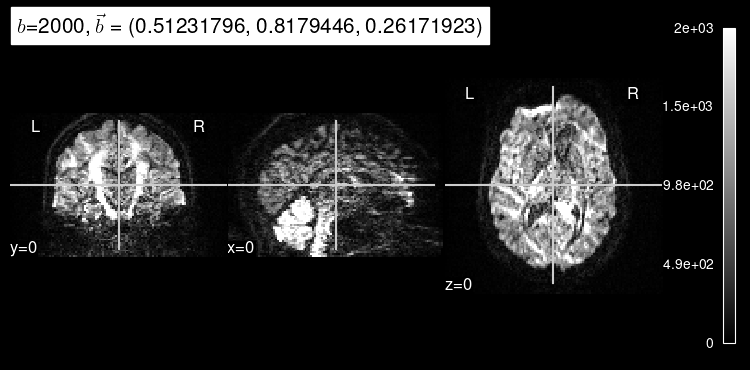

Now, the predicted map for the particular b gradient looks much closer to the original:

plot_dwi(predicted, dmri_dataset.affine, gradient=data_test[1], black_bg=True);

Here’s the original DW map, for reference: